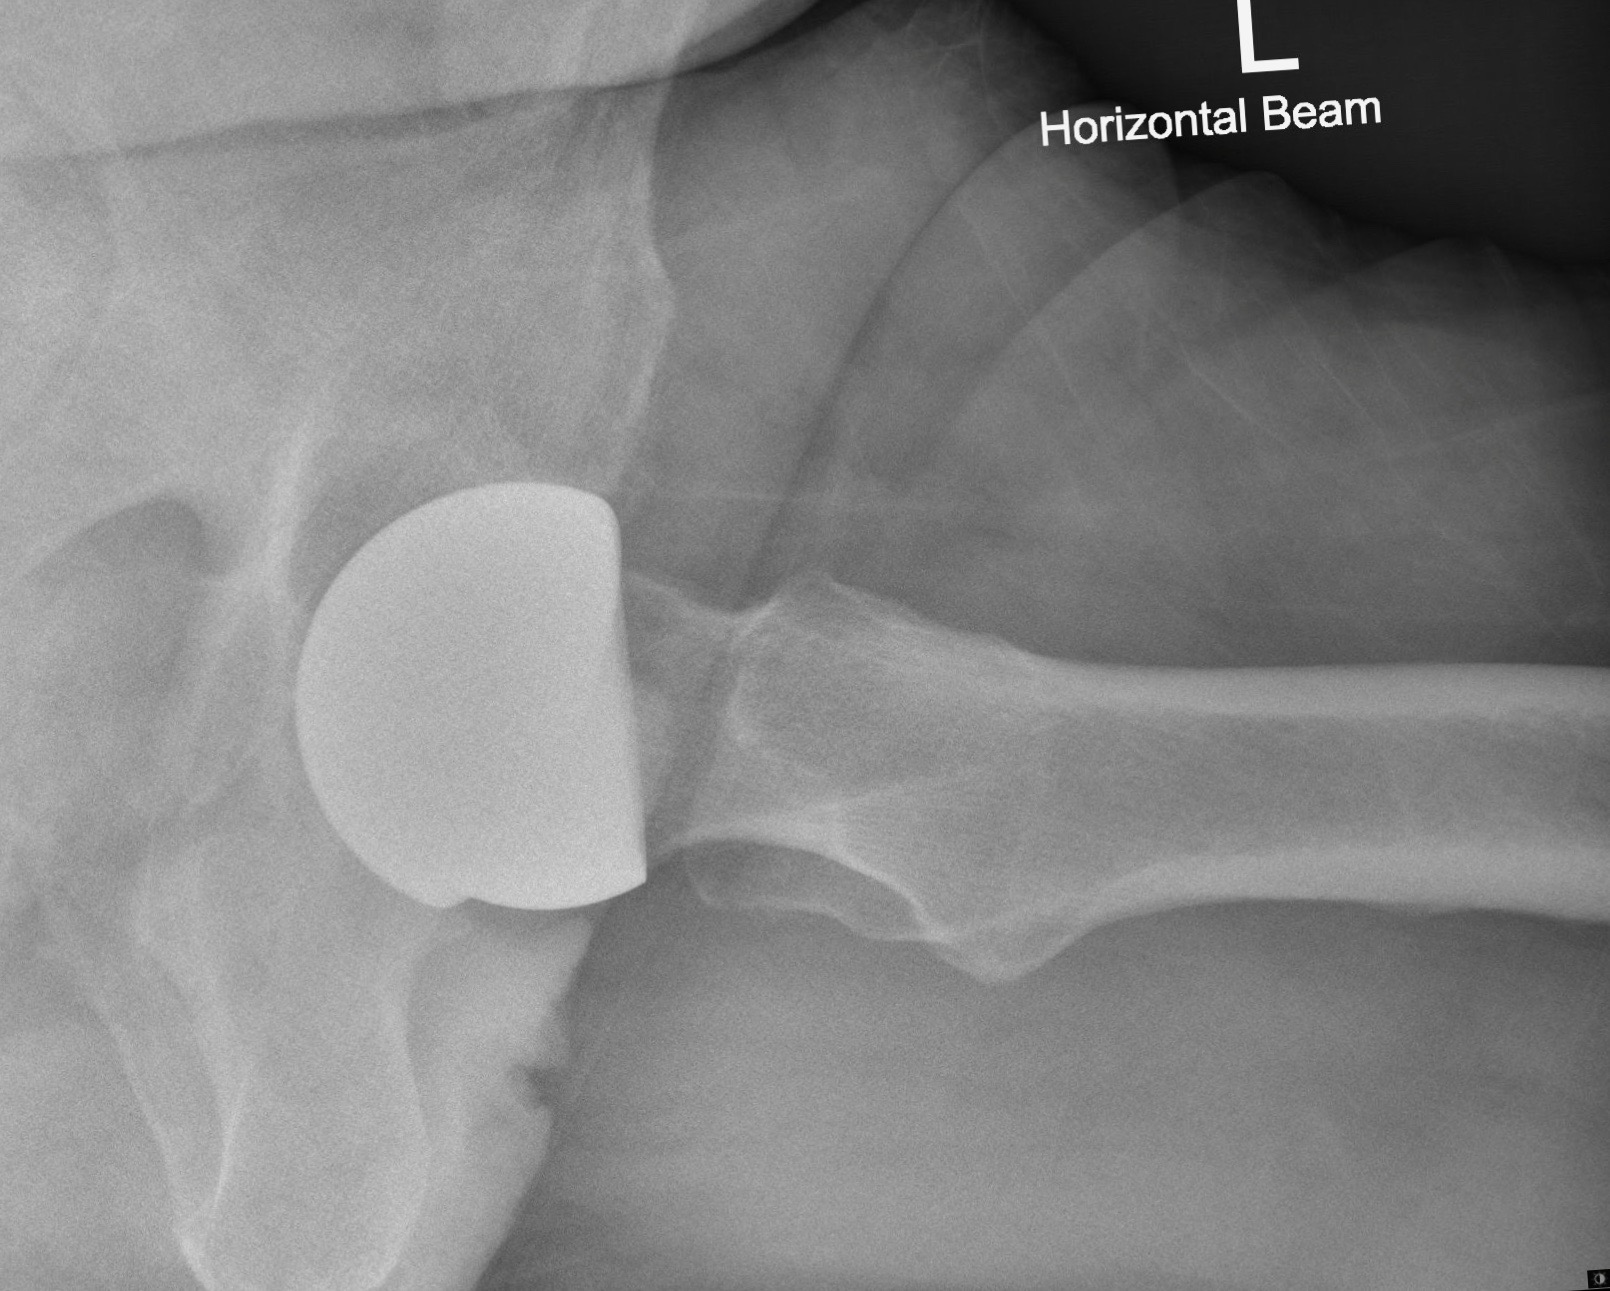

At the time of surgery, via a standard posterior approach, using exactly the same exposure and release as required for a metal-on-metal hip resurfacing, a ReCerf® device was implanted. The 56mm colour-coded socket was implanted using a specifically designed acetabular insertion device, used alongside the standard ADEPT® socket insertion handle and alignment jig. Socket position was targeted at between 35 and 40 degrees of abduction with anteversion matching the native socket and the transverse acetabular ligament, typically around 15 degrees.

The standard ADEPT® medial referencing jig was used to position a guide wire into the femoral head and neck, determining bone preparation and component position. Again, the same instrumentation used for the ADEPT® device is used with ReCerf®. With preparation complete, a compatible and similarly colour-coded 50mm femoral component was cemented in place, using standard cement fixation and impaction technique to the established ADEPT® metal-on-metal device. (As such the ReCerf® concept uses of the majority of the ADEPT® metal-on-metal instrumentation and would therefore provide the surgeon with the opportunity to determine bearing surface material with flexibility intraoperatively.)

The patient’s progress was reviewed initially at 6 weeks and again at 3 months. By 10 weeks the patient had already regained largely normal function, in part likely due to his strong drive and determination to return to his desired level of activity. In fact he had already re-started his climbing with confidence and control perhaps a little earlier than his surgeon would have advised, but without concern, as demonstrated in figure 3.